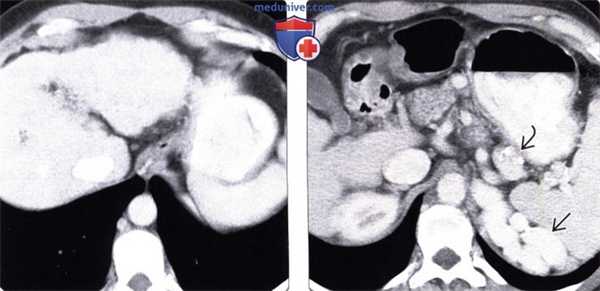

(Слева) На аксиальной КТ с контрастным усилением у мужчины среднего возраста, страдающего циррозом печени, определяются признаки цирроза и, в то же время, относительно небольшие варикозно расширенные вены пищевода. Воротная вена тромбирована (не показана).

(Справа) На аксиальной КТ с контрастным усилением у этого же пациента визуализруются расширенные в значительной степени, варикозно измененные околоселезеночные вены, а также кальцинаты в стенке некоторых из них, что может привести к ошибочному выводу об аневризме.